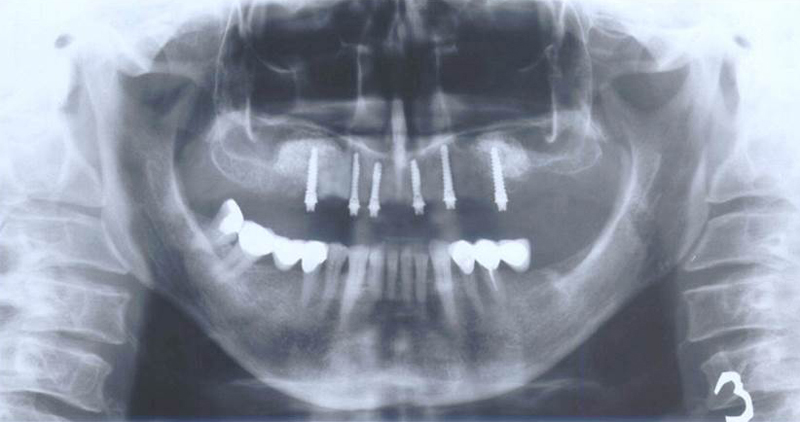

Nejčastější oblastí pro doplnění kosti je čeleni dutina horní čelisti.

Tento výkon se nazývá sinus lift - aplikace kostního granulátu do čelistní dutiny

Při ztrátě molárů a premolárů v horní čelisti a jejich náhradě implantáty se často setkáváme s nedostatečnou vertikální nabídkou kosti pod čelistní dutinou, často doprovázenou i nedostatečnou horizontální nabídkou a sníženou kvalitou kosti

(v oblasti 2. premoláru v 50%, v oblasti moláru až v 80% případů nedostatečná kostní nabídka)

Od roku 1985 je tento problém řešen augmentační operací nazývanou sinus lift.

Jedná se o vyzvednutí membrány, která čelistní dutinu vystýlá, pod vyzvednutou membránou vznikne kapsa, kam se umístí augmentační materiál, do kterého se zavedou implantáty.

Vhojení implantátů se při této operaci prodlužuje na 6-12 měsíců.